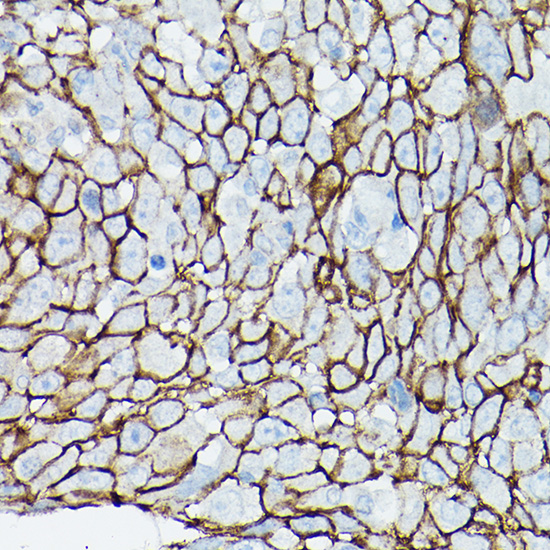

Immunohistochemistry of paraffin-embedded human prostate cancer using ??-Catenin/p120 Catenin Rabbit pAb.

,

Immunohistochemistry of paraffin-embedded human urothelial carcinoma using ??-Catenin/p120 Catenin Rabbit pAb.